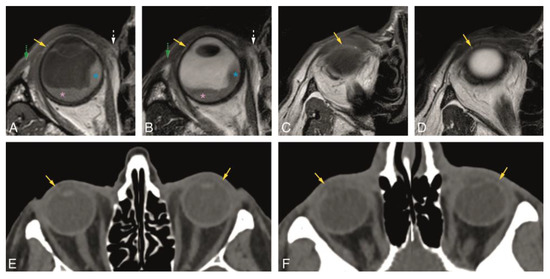

In Groups 1 and 2, we evaluated normal eyelid anatomy on MRI and CT, respectively. On MRI, this was best achieved on the T1 and T2 sequences without fat suppression and without contrast. All eyelid layers could be identified, except for the tarsal muscles on CT and for the conjunctiva both on CT and MRI. The skin was isointense or slightly hyperintense to muscle on T1-WI and T2-WI and isodense on CT. Behind the skin, the layer with loose connective tissue had fat signal intensity and density on MRI and CT, respectively, not always being visualized on CT. The orbicularis oculi muscle was well recognized on MRI [17] and CT and seen extending peripherally beyond the edge of the anterior orbital rim. The second layer of loose connective tissue lying behind the orbicularis oculi muscle had the same imaging characteristics as the first connective tissue layer. The fifth layer of each eyelid was formed centrally by the tarsal plate and peripherally by the orbital septum. The superior and inferior tarsal plates appeared as a posterior concave or crescent-shaped line with several dots with signal intensity [15] and density of fat on MRI and CT, respectively, due to the sebaceous content of the meibomian glands. Although this characteristic pattern with several dots was more readily visible on MRI, it can be recognized on CT. On MRI, the superior and inferior orbital septa appeared as hypointense on T1-WI and hypointense on T2-WI, contrasting with the surrounding hyperintense fat [2,13]. On CT, they were hyperdense, in opposition to the adjacent hypodense fat. The sixth layer of the eyelids consists of the tarsal muscles, identified on MRI [2,17] and not identified on CT. The most posterior layer of the eyelid, the conjunctiva, was not seen either on MRI or on CT (Figure 2, Figure 3 and Figure 4).

In Group 1, the visibility of the superior and inferior tarsal plates and orbital septa was scored on MRI (Table 1). Both the superior and inferior tarsal plates were identifiable in 94% of the subjects, being the superior tarsal plate well-defined in 78% and the inferior tarsal plate well-defined in 67% of the subjects. The superior tarsus was easier to identify on the axial plane. The inferior tarsus was equally well visible on the axial and sagittal planes (Figure 2A,E,F, and Figure 3A–D). The superior septum was always visible, being well-defined in 92% of the subjects. The inferior septum was visible in 91% of the subjects, but it was well-defined in only 36% of the subjects. The superior and inferior septa were easier to identify on the sagittal plane (Figure 2A,B,E,F, and Figure 4A–D). Orbital septa and tarsal plates were more difficult to identify when the slices were not acquired perpendicular to the main axis of the eyelid, and when movement artifacts were present. In Group 2, and similarly to Group 1, the superior and inferior tarsal plates and orbital septa were scored (Table 2). The superior tarsus was always visible, being well-defined in 63% of the subjects. The inferior tarsus was visible in 84% of the subjects and was well-defined in 53% of the subjects. Both the superior and inferior tarsal plates were better depicted on the axial plane than on the sagittal plane (Figure 2G and Figure 3E,F). The superior septum was visible in 89% of the subjects and well-defined in 47% of the subjects. The inferior septum was visible in 68% of the subjects, but well-defined only in 11% of the subjects. The superior and inferior septa were easier to identify on the axial plane (Figure 2C,G and Figure 4E,F) than on the sagittal plane.

Figure 3. A, B, and E: Normal superior tarsal plate (yellow arrow) on the axial plane on MR T1-WI (A), T2-WI (B), and on CT (E). Notice, at A and B, the uveal melanoma (blue asterisk) with associated retinal detachment (pink asterisk), impossible to differentiate on non-contrast enhanced sequences. C, D, and F: Normal inferior tarsal plate (yellow arrow) on the axial plane on MR T1-WI (C), T2-WI (D), and on CT (F). Yellow arrow: superior and inferior tarsal plates; green dashed arrow: lateral palpebral ligament region; white dashed arrow: medial palpebral ligament region; blue asterisk: uveal melanoma; pink asterisk: retinal detachment.

Figure 4. A, B, and E: Normal superior orbital septum (blue arrow) on the axial plane on MR T1-WI (A), T2-WI (B), and on CT (E). C, D, and F: Normal inferior orbital septum (blue arrow) on the axial plane on MR T1-WI (C), T2-WI (D), and on CT (F). Blue arrow: orbital septum; red asterisk: lacrimal gland.